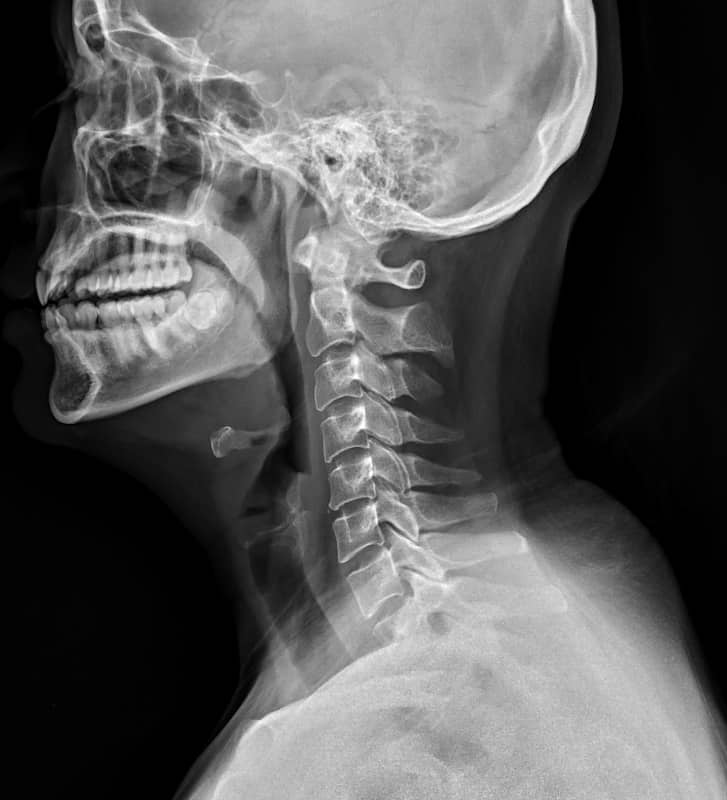

In most cases, cervical spondylosis can be suspected or diagnosed through the clinical features (what it looks like and how it behaves), your symptoms (what you tell us about your neck) and the clinical assessment (testing the movements etc.). An X-ray of the neck can be used to help diagnose spondylosis but is not always required.

In a lot of cases, the information we as healthcare professionals can get from asking you questions and testing the neck is enough to make a decision. X-rays are a very useful tool as they show you what your neck looks like on the inside, however in some cases what your neck looks like on the inside doesn’t really marry up with what your problem might be.

There is growing evidence (experiments and clinical studies) that demonstrate what you see is not always what you get with X-rays and scans, and that a lot of the so-called ‘worn out’ or ‘abnormal’ findings are seen commonly in people with no pain, stiffness or symptoms.